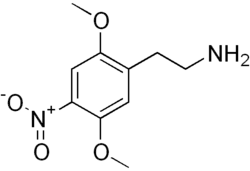

Activation of the 5-HT2A receptor is necessary for the effects of the "classic" psychedelics like LSD, psilocin and mescaline, which act as full or partial agonists at this receptor, and represent the three main classes of 5-HT2A agonists, the ergolines, tryptamines and phenethylamines, respectively. A very large family of derivatives from these three classes has been developed, and their structure-activity relationships have been extensively researched.[70][71] Agonists acting at 5-HT2A receptors located on the apical dendrites of pyramidal cells within regions of the prefrontal cortex are believed to mediate hallucinogenic activity. Some findings reveal that psychoactive effects of classic psychedelics are mediated by the receptor heterodimer 5-HT2A–mGlu2 and not by monomeric 5-HT2A receptors.[72][73][57] However, newer research suggests that 5HT2A and mGlu2 receptors do not physically associate with each other, so the former findings have questionable relevance.[74] Agonists enhance dopamine in PFC,[33] enhance memory and play an active role in attention and learning.[75][76]

Serotonin 5-HT2A receptor agonists include serotonergic psychedelics[77] and non-hallucinogenic agents.[78][79] Psychedelics have widely been encountered as recreational drug or drugs of misuse, with potential clinical consequences such as overdose, hospitalization, bad trips and worsened mental health, and rare adverse effects such as seizures, psychosis, and hallucinogen persisting perception disorder (HPPD).[80][81] On the other hand, psychedelics and non-hallucinogenic serotonin 5-HT2A receptor agonists are under development as novel treatments for psychiatric disorders like depression, anxiety, and addiction as well as other conditions like cluster headaches.[82][83][84][85][86] Both psychedelics and non-hallucinogenic serotonin 5-HT2A receptor agonists are claimed to act as psychoplastogens and this might be involved in their therapeutic effects.[85][87][88]